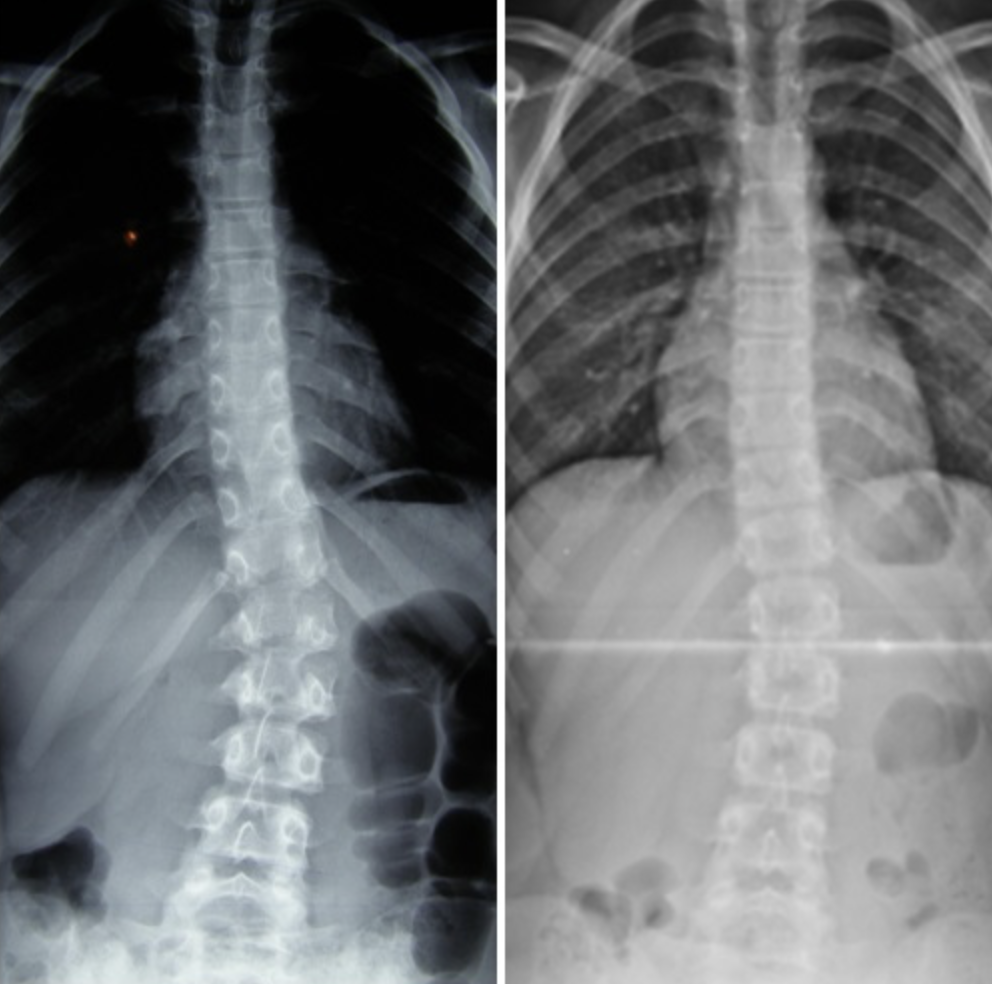

Martyna – 10 lat

Terapia prowadzona w okresie 03.10.2016 – 02.01.2017 (20 zabiegów) Częstotliwość zajęć – 2 x tydz. Po skończonej terapii dziecko było pod kontrolą naszego ośrodka. W lutym 2019 zrobiono zdjęcie RTG, które nie wykazało skrzywienia kręgosłupa.